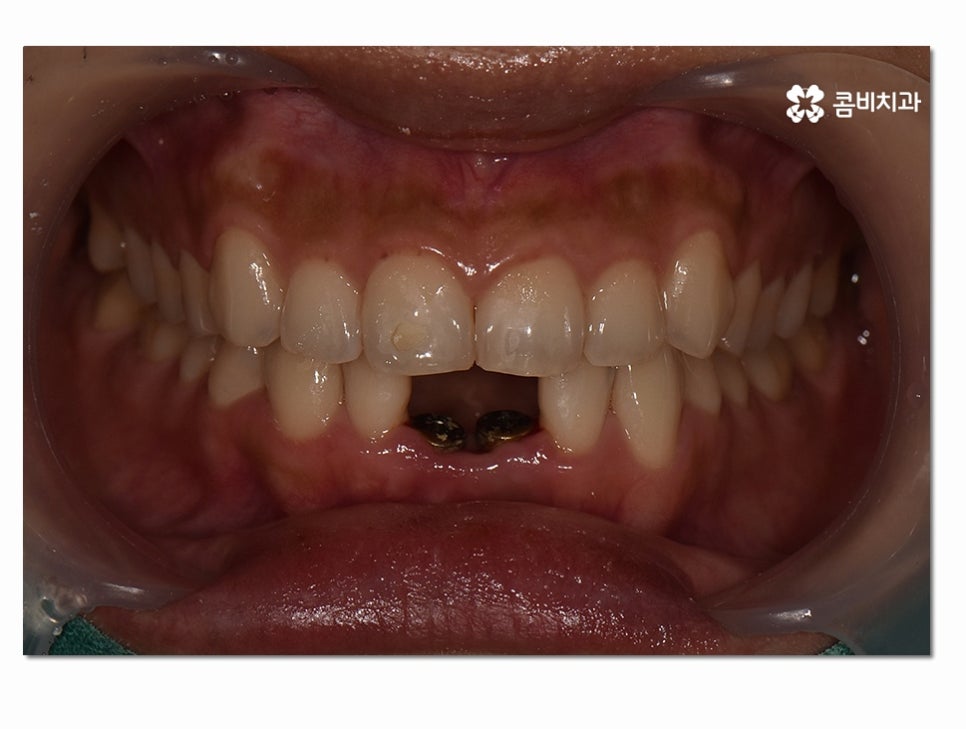

오늘은 위 이미지처럼 실제로 아랫니 임플란트 진행된

사례를 통해 시술 과정에 대해 자세하게 알아보도록 할 거예요.

위 환자분의 경우 잇몸질환이 심해져서 치아 뿌리까지

염증이 심해졌고 결국 발치까지 하게 된 사례인데

치주염이 심해지기 전까지 제대로 된 치료를 하지 않아

결국 발치까지 하게 된 경우라고 할 수 있어요.